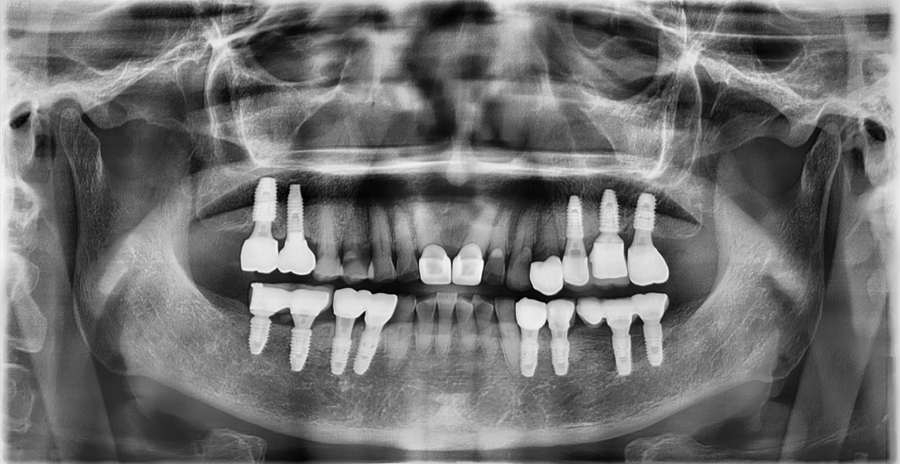

발치 후 임플란트 치료로 기능과 심미를 회복한 사례입니다.